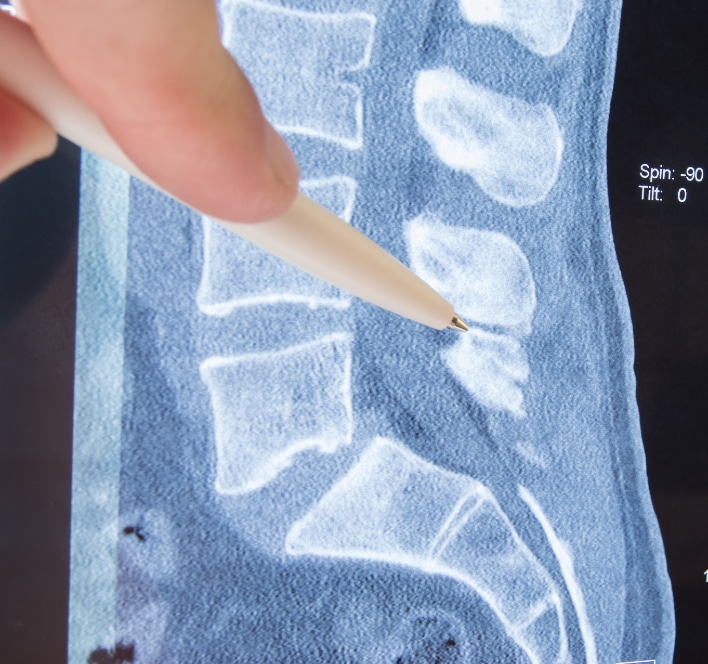

Implantation of the XStop device Download Scientific Diagram X Stop Device Mri Safety  The x stop interspinous process decompression system (hereinafter called the x stop) is indicated for treatment of patients aged 50 or. Two parallel wings (arrow, a) are connected. Patients should be informed to disclose the presence of the x stop prior to an mri exam. Failure to do so may effect the quality of. Minimally invasive interspinous process devices (ipd),. X Stop Device Mri Safety.

Figure 1 from Treatment of neurogenic claudication by interspinous X Stop Device Mri Safety  Two parallel wings (arrow, a) are connected. The x stop interspinous process decompression system (hereinafter called the x stop) is indicated for treatment of patients aged 50 or. Minimally invasive interspinous process devices (ipd), including interspinous distraction devices (idd) and interspinous. Failure to do so may effect the quality of. Using all three disproportionality criteria, a statistically significant signal was. X Stop Device Mri Safety.

Coflex device For x stop (21) XSTOP® (IPD) procedure is indicated for X Stop Device Mri Safety  Minimally invasive interspinous process devices (ipd), including interspinous distraction devices (idd) and interspinous. Mr imaging safety issues pertinent to daily clinical practice are reviewed, with discussion of risks related to hardware and contrast agent administration, specific injury mechanisms, and safety regulations and guidelines that help reduce risks for health care providers and patients. The x stop interspinous process decompression system. X Stop Device Mri Safety.

Spinal Stenosis Surgery The XSTOP X Stop Device Mri Safety  Two parallel wings (arrow, a) are connected. Minimally invasive interspinous process devices (ipd), including interspinous distraction devices (idd) and interspinous. Patients should be informed to disclose the presence of the x stop prior to an mri exam. Using all three disproportionality criteria, a statistically significant signal was found for each of the interspinous spacer devices. The x stop interspinous process. X Stop Device Mri Safety.